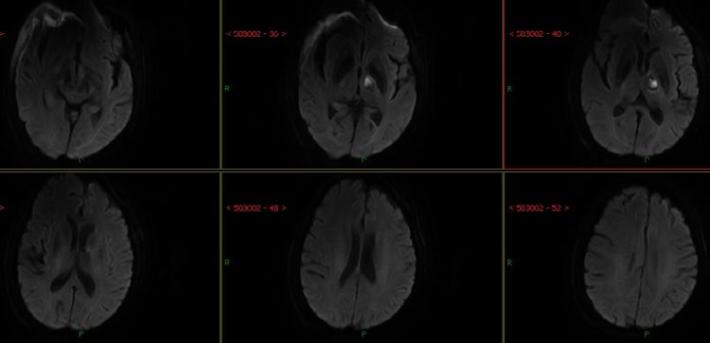

入院急查血未见明显异常指标,急查头部MRI+MRA:右侧半卵圆中心、右侧侧脑室旁多发急性脑梗死,右侧大脑中动脉重度狭窄,分枝稀疏。

术后24天复查头部MRI+MRA

术后8天复查头部MRI